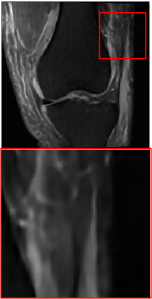

Figure 5 provides the qualitative comparison of the various methods on the four datasets at a scale of 4. The top, second, third, and bottom rows are the SR results under the FastMRI, clinical brain, clinical tumor and clinical pelvic datasets, respectively. The red boxes indicate the zoom-in region of complicated anatomical structures along with their corresponding error maps. Note that the brighter textures in the error maps, the lower the quality of the reconstructed images. As can be seen, compared to methods based on Transformers and CNNs, diffusion-based methods like DisC-Diff and DiffMSR (Ours) are capable of reconstructing high-realistic images with promising reconstruction metric scores (PSNR and SSIM). Nevertheless, while DisC-Diff can reconstruct high-precision MR images, it does not preserve the structure present in the original HR images, introducing some additional information that can affect medical diagnosis. In contrast, our method combines DM and PLWformer, which can preserve the original image’s structure while restoring high-frequency information.